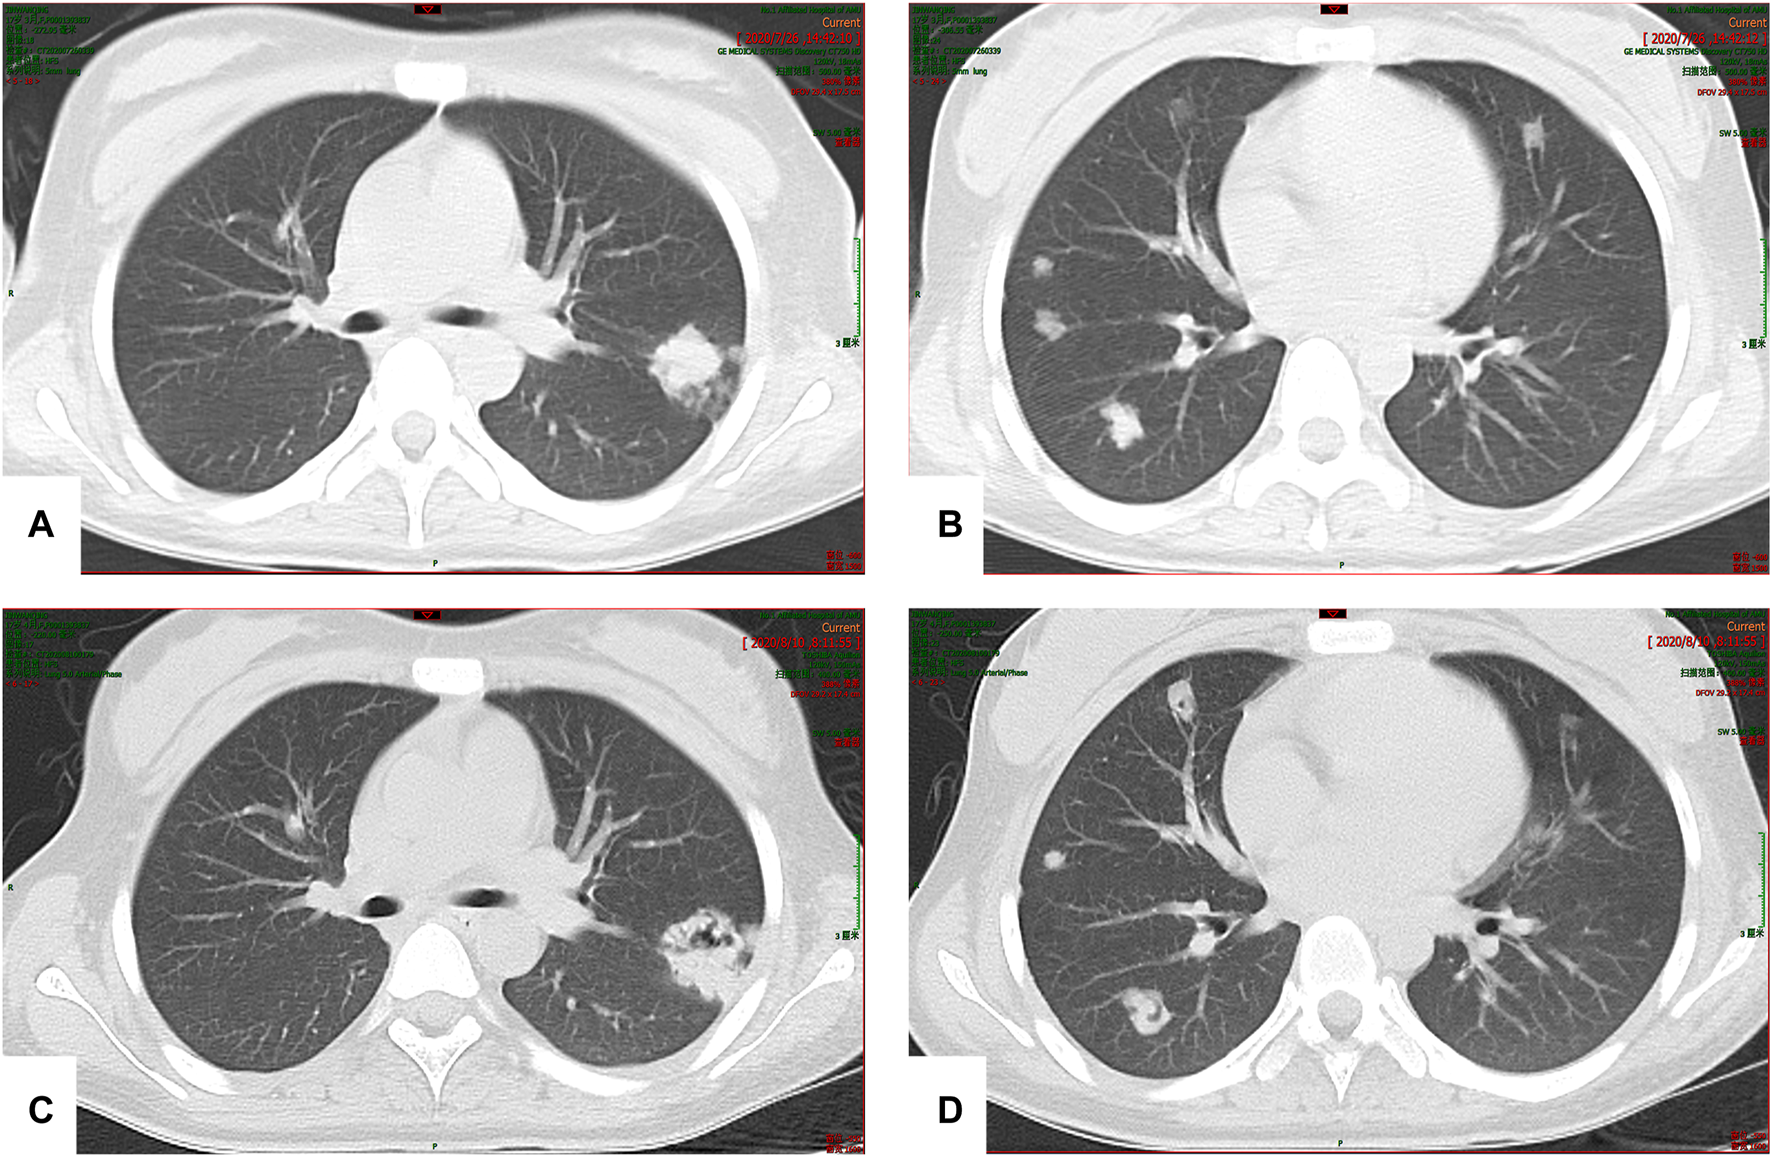

The patient developed hepatic encephalopathy and frequent vomiting on day 4, and she was placed on the liver transplant waiting list. She was treated with dexamethasone (10 mg q.d. i.v., gradually decreased after 3 days), liver protection, and NBAL (from July 7 to July 20, once every 3–4 days), and her liver function rapidly improved. After 10 days in a comatose state, she regained consciousness. She continued to have an intermittent low-grade fever on 24 July 2020, and no cough or other symptoms. Her TBil level had increased to 388 μmol/L, and the white blood cell (WBC) count was 12.13 × 109/L with 83.50% neutrophils. Her chest CT scan showed multiple nodules in both lungs on July 26 (Figures 3A,B), and IFI was diagnosed. A loading dose of caspofungin of 70 mg q.d. ivgtt was given on the first day, and then it was continued at a dose of 35 mg/d ivgtt for 23 days. However, a repeat chest CT showed an increase in the number of lung lesions and the presence of an air crescent sign (Figures 3C,D). Bronchoalveolar lavage fluid (BALF), G test, GM test, and next-generation sequencing (NGS) were all negative; however, based on her history and chest CT findings, a diagnosis of IPA was highly likely. Caspofungin was changed to voriconazole (loading dose on D1 of 6 mg/kg daily q12 h ivgtt, maintenance dose of 4 mg/kg q12 h orally was started on D2) on 19 August 2020, and her liver function gradually improved. A liver biopsy on 25 August 2020 was consistent with DILI (G 3–4 S 3–4) (Figures 4A,B). She was discharged on oral voriconazole (250 mg, q12 h), methylprednisolone (4 mg, q.d.), and other medications. A second liver biopsy after 10 weeks revealed an autoimmune-like phenomena hepatitis (G 1–2 S 2–3) (Figures 4C,D). A liver biopsy was performed, and ink staining, periodic acid–Schiff staining, hexamine silver staining, acid-fast staining, and NGS of liver tissue were negative. A diagnosis of DILI was made according to the RUCAM and 2008 IAIHG criteria: (1) DILI, hepatocellular damage-type, acute, RUCAM score calculated as 9 (highly likely); (2) IAIHG score 4, the diagnosis of DILI with autoimmune-like phenomena.

FIGURE 3. (A,B) Multiple nodular high-density shadows were observed in both lungs; the larger one was located in the upper lobe of the left lung (20 × 24 mm). (C,D) After 2 weeks of treatment, multiple nodular high-density shadows were observed in both lungs; the larger one was 29.4 × 28.4 mm in size, and voids were present in some lesions.